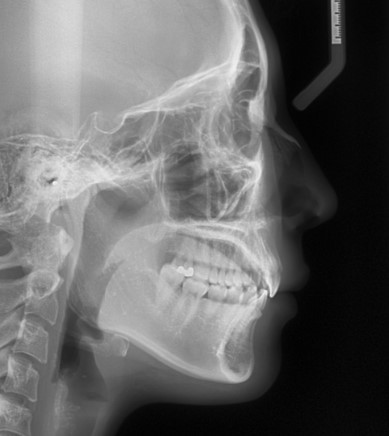

원인 분석: 치아 위치·각도·위턱뼈까지 함께 보는 진단

이제 이 분의 거미스마일 원인을 조금 더 자세히 분석해 보겠습니다.

엑스레이를 통해 확인해 보니, 치아의 수직 위치가 약간 내려와 있는 부분도 있었지만,

그보다 더 중요한 것은 위 앞니의 각도가 너무 “직립”되어 있고, 위턱뼈 자체가 전방으로 돌출된 형태라는 점이었습니다.

즉, 치아가 뻐드러져서만 생긴 거미스마일이 아니라,

치아 각도,

위턱뼈의 위치,

웃을 때 입술이 움직이는 패턴

이 모두 영향을 주면서 잇몸이 많이 드러나는 케이스였습니다.

이처럼 치아가 수직으로 심하게 내려오거나, 눈에 띄게 뻐드러져 있지 않더라도,

치아의 각도나 골격 위치가 입술 움직임과 만나면서 거미스마일을 만드는 경우가 있습니다.

이 환자분의 경우는 돌출이나 덧니가 두드러진 상황은 아니었기 때문에, 비발치 교정으로 치료하기로 계획을 세웠습니다.